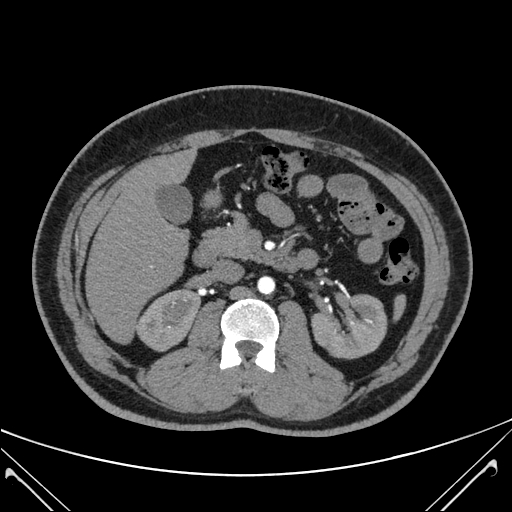

Computed Tomography (CT)

CT scans produce detailed 3D images of your pet’s internal structures, helping us assess bones, joints, lungs, and organs with high precision. It’s especially useful for trauma cases, cancer investigations, and planning complex surgeries.